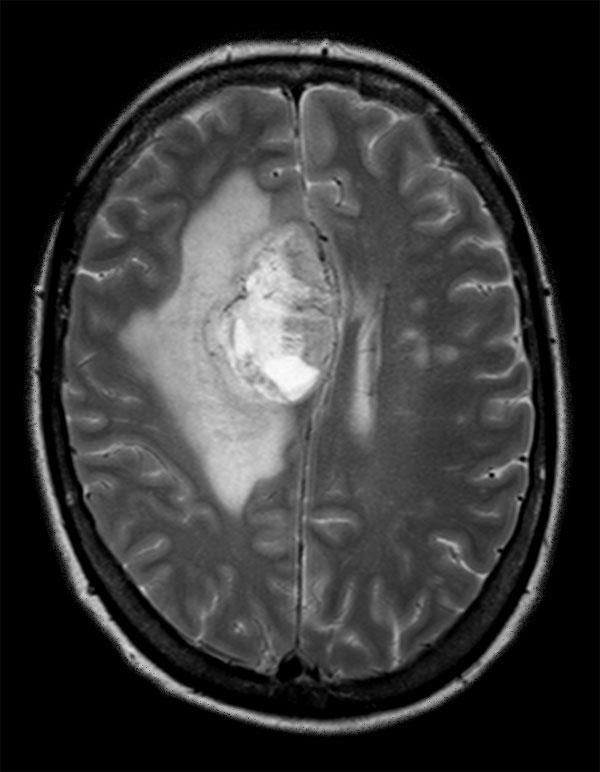

Advanced Neuro imaging - pCASL

Clinique Saint Joseph Imagerie Medicale, Liege, Belgium